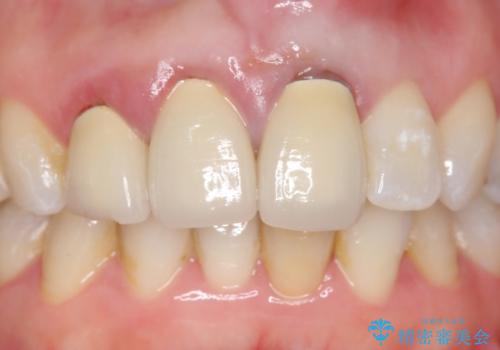

根尖病変を認めたため再根管治療を行った後、オールセラミッククラウン(スペシャル)にて補綴を行いました。

- オールセラミッククラウン(スペシャル)…¥130,000×3、仮歯…¥10,000×3、ファイバーコア…¥20,000×3費用は治療当時の料金となります

前歯の補綴ではオールセラミッククラウンを希望される患者様が多いですが、オールセラミッククラウンの中でも、エコノミー、スタンダード、スペシャル、エクセレントとランクがあります。

その中でも特に審美性が高いのがスペシャル、エクセレントです。スペシャル、エクセレントは口腔内写真をもとに熟練の技工士が、患者様の口腔内に合わせたオーダーメイドのクラウンを製作致します。